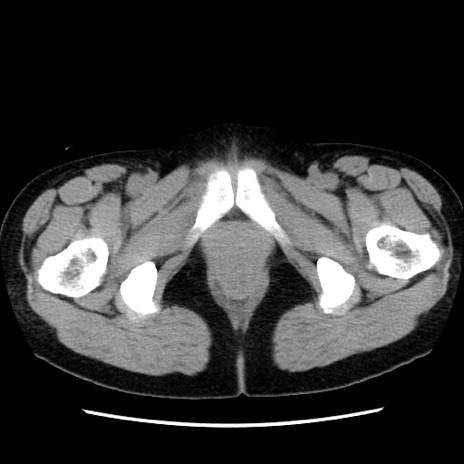

症例10(横断像)

【症例】 50歳代女性

【主訴】 腹痛

【現病歴】前日生レバーを食べた。今朝に排便あり。 昼前に突然発症の腹痛を生じ、当院救急外来を受診した。

【既往歴】 子宮筋腫にてで子宮全摘後

【身体所見】 意識清明、腹部:平坦、軟、下腹部やや左を中心に圧痛・反跳痛あり、筋性防御あり

【データ】WBC 7800、CRP 0.07